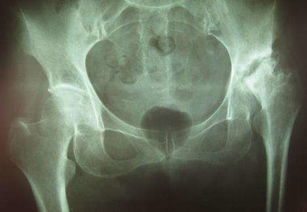

我們分析一下股骨頭壞死?,F在的股骨頭壞死主要是缺血性無(wú)菌型股骨頭壞死,通常簡(jiǎn)稱(chēng)股骨頭壞死。這種股骨頭壞死,是因為血管堵塞、股骨頭的骨細胞缺氧、缺水、缺營(yíng)養紛紛死亡,所謂的“股骨頭壞死”并不是股骨頭里所有的骨細胞都死光光。事實(shí)上,即使是壞死很?chē)乐氐墓晒穷^里面,都或多或少存在著(zhù)活的骨細胞,要不然股骨頭早就萎縮消失了。因此,只要恢復向股骨頭供血,那些活著(zhù)的骨細胞就因為得到更多的氧氣、水和營(yíng)養,就能夠進(jìn)行高速度的細胞分裂,實(shí)現包括骨細胞、各種軟組織細胞在內的細胞大量增殖(這和“有了充足的磚瓦水泥鋼材等,就可以建起大量樓房”一個(gè)道理)。

股骨頭壞死,又稱(chēng)股骨頭缺血性壞死,為常見(jiàn)的骨關(guān)節病之一。

大多因風(fēng)濕病、血液病、潛水病、燒傷等疾患引起。至于它用什么方法治療比較好,這要看而定者的股骨頭的塌陷程度。